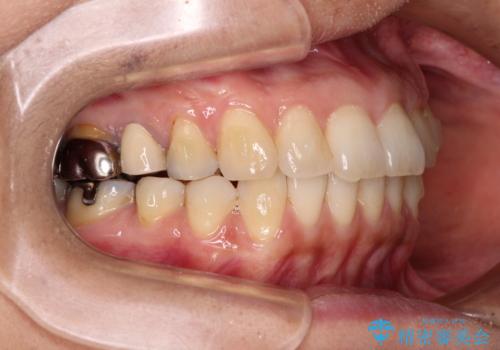

- 高校生の時に行った矯正治療の後戻りと、通院してもなかなか改善しない奥歯の痛みを気にして来院された患者様です。

左下奥歯は、前医より難治性なので抜歯も考えるよう言われたそうですが、一度もラバーダムを用いた根管治療はされていないとのことでした。

まずは左下奥歯の根管治療を行い、痛みが引いたことを確認してから矯正治療を開始しました。

矯正治療後には、左下奥歯の症状がないことを確認し、セラミッククラウンにて補綴治療を行うこととしました。